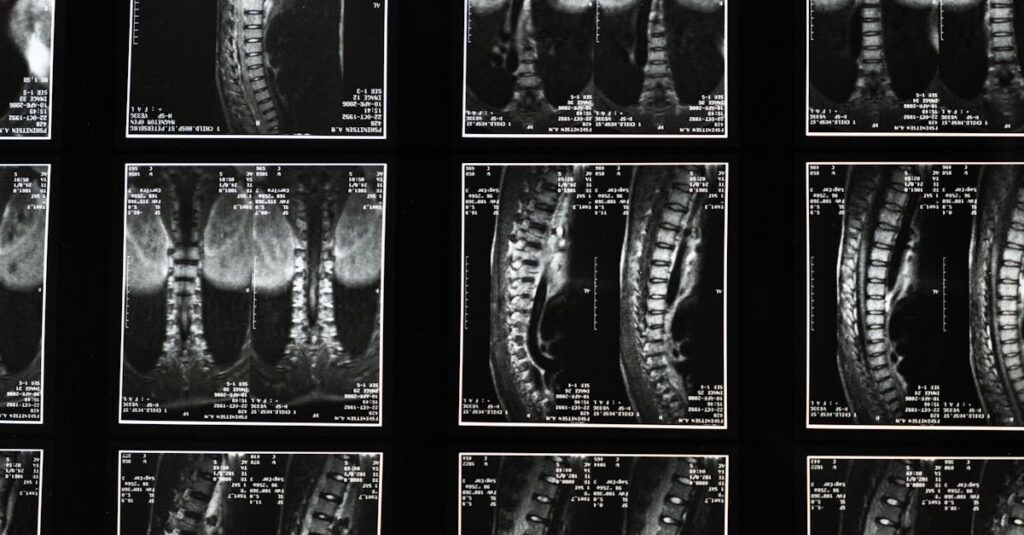

La décompression spinale est une technique thérapeutique non invasive conçue pour soulager les douleurs associées aux pathologies de la colonne vertébrale, comme les hernies discales ou les douleurs lombaires. Elle utilise un dispositif spécialisé pour réduire la pression exercée sur les disques intervertébraux et les nerfs de la colonne. Ce traitement a pour but d’améliorer la circulation sanguine et de favoriser ainsi la guérison des tissus affectés.

La décompression spinale a pour objectif de réduire la pression sur les disques intervertébraux et les nerfs de la colonne vertébrale en créant un espace entre les vertèbres. Cela permet à de nombreux patients qui souffrent de conditions comme les hernies discales ou la sténose spinale de retrouver mobilité et confort sans avoir recours à des interventions chirurgicales invasives. Cependant, des scepticismes demeurent concernant son efficacité réelle.